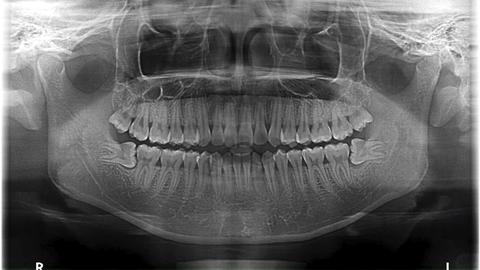

双侧低位阻生智齿

低位埋伏水平阻生智齿拔除

低位全埋伏阻生智齿

长了四颗智齿,下面两颗是全埋伏低位水平阻生,不疼,可以不拔吗?

超低位阻生齿图片